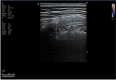

A novel coronavirus (2019-nCoV) was identified as the cause of a cluster of pneumonia in Wuhan, China, at the end of 2019. Since then more than eight million confirmed cases of coronavirus disease 2019 (COVID-19) have been reported around the globe. The current gold standard for etiologic diagnosis is reverse transcription-polymerase chain reaction analysis of respiratory-tract specimens, but the test has a high false-negative rate owing to both nasopharyngeal swab sampling error and viral burden. Hence diagnostic imaging has emerged as a fundamental component of current management of COVID-19. Currently, high-resolution computed tomography is the main imaging tool for primary diagnosis and evaluation of disease severity in patients. Lung ultrasound (LUS) imaging has become a safe bedside imaging alternative that does not expose the patient to radiation and minimizes the risk of contamination. Although the number of studies to date is limited, LUS findings have demonstrated high diagnostic sensitivity and accuracy, comparable with those of chest computed tomography scans. In this note we review the current state of the art of LUS in evaluating pulmonary changes induced by COVID-19. The goal is to identify characteristic sonographic findings most suited for the diagnosis of COVID-19 pneumonia infections.